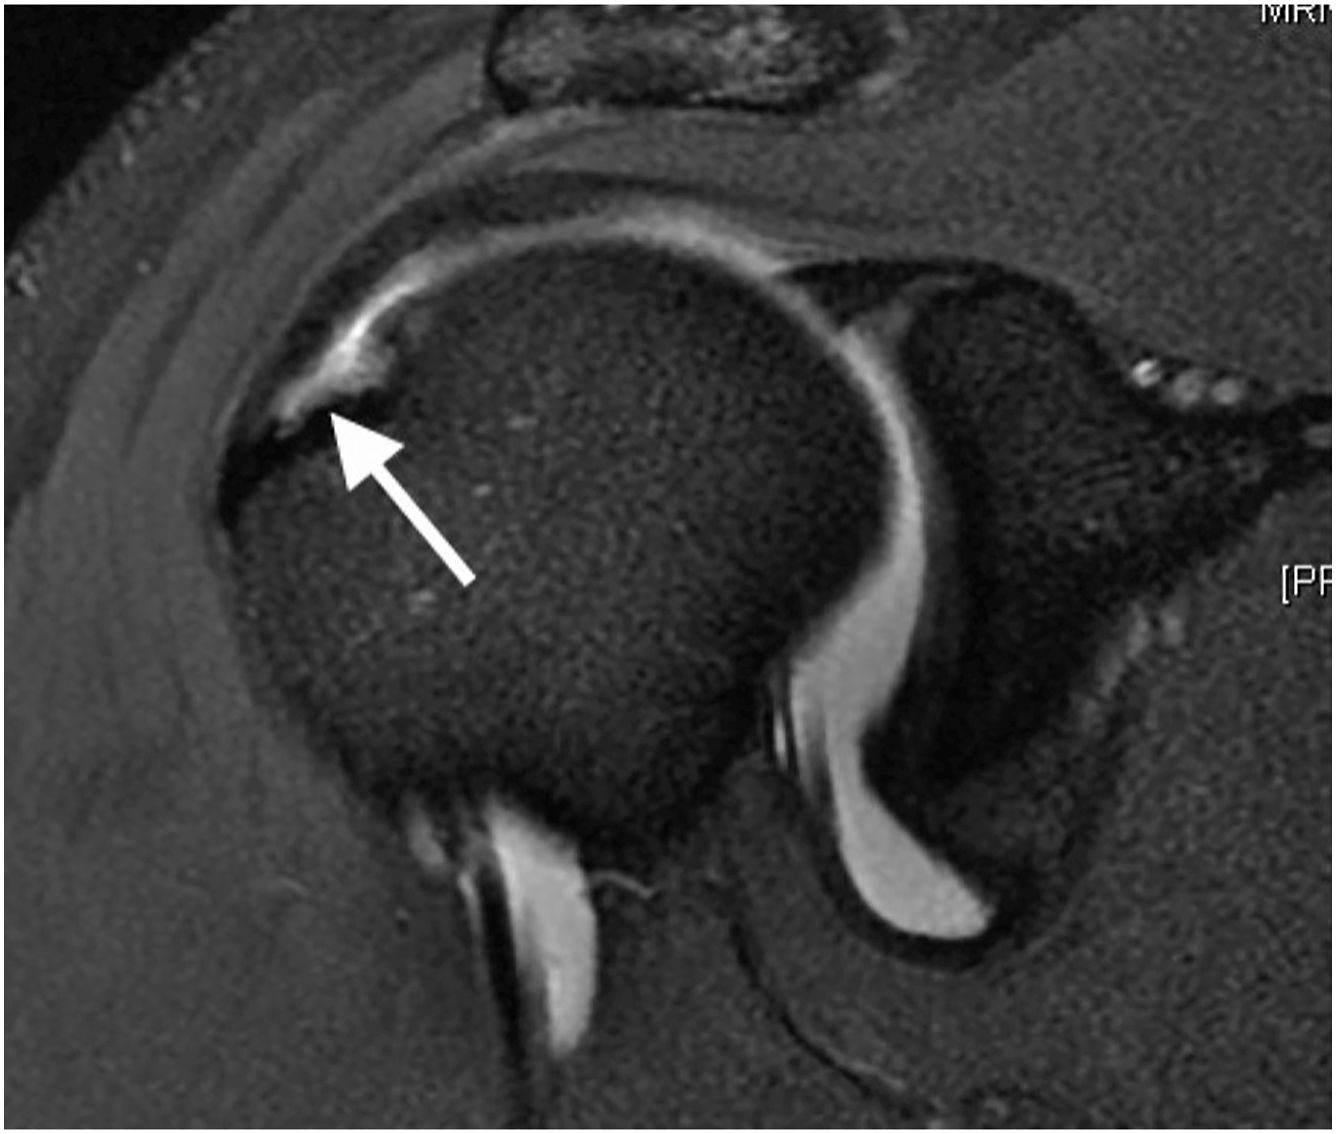

Initially observed by Walch and colleagues, the term internal impingement describes the natural phenomenon of contact between the articular surface of posterior supraspinatus and superior infraspinatus along the posterior superior glenoid when the arm is placed in 90° of abduction and 90° of external rotation. In an arthroscopic study, McFarland and colleagues noted a variety of arm positions can lead to impingement and it is the repetitive nature that leads to rotator cuff issues. Burkhart and colleagues viewed internal impingement as a natural variant with the shear and torsional forces experienced by the rotator cuff due to posterior capsular contracture. Ultimately, this leads to abnormal humeral head motion and a posterior superior shift of the center of rotation when the arm is placed in hyperexternal rotation. While total arc of motion could be preserved in GIRD, as the throwing motion progresses to the maximally abducted and externally rotated position, the contracted posterior capsule initiates a pathologic cascade. This cascade results in relative posterior superior translation of humeral head, loosening of the anterior inferior glenohumeral ligament, and placement of the undersurface of the posterior supraspinatus and anterior infraspinatus into contact with the posterior superior glenoid. (p1), It is important to note that asymptomatic rotator cuff tears are common in baseball players and considered adaptive for internal impingement ( Fig. 1 ). Sabick and colleagues reported the throwing shoulder in professional baseball pitchers experiences a degree of both repetitive angular velocity and forces across the joint that surpasses the torsional failure limit in human cadavers. Lesniak and colleagues, in the MRI study of asymptomatic major league pitches, reported a correlation between higher cumulative innings pitched and increased likelihood of rotator cuff tear, independent of symptoms. Partial rotator cuff tears in baseball pitchers may be asymptomatic as a result of these adaptive changes in contrast to the rare full-thickness tears which are more commonly associated to a single traumatic event, often seen in contact athletes. In fact, studies report more than 40% rate of completely asymptomatic partial articular lesions in professional pitchers. Therefore, the presence of positive imaging findings in asymptotic throwers may warrant no intervention or treatment.

Operative treatment is reserved for those throwers who failed nonoperative management and those who were not able to adequately progress through a return to throwing program. There are important considerations when repairing the rotator cuff in the baseball athlete. The goal for surgical treatment of rotator cuff pathology in the baseball athlete is to respect the adaptive anatomic changes related to throwing aiming to avoid over-tensioning of the tendon as this will limit abduction and external rotation. For shallow articular sided tears, less than 50% of the footprint, arthroscopic debridement is indicated with the goal to debride the tear down to stable margins along with debridement of inflamed synovial tissue. These lesions are referred to as partial-thickness articular supraspinatus tear avulsion (PASTA) lesions. The concern regarding traditional repair in PASTA lesions is over-tensioning, as the lesions is more due to tissue loss than peel back phenomenon in non-thrower rotator cuff injuries. Lesions with delamination of the rotator cuff tear such that the articular side is detached and mobile from the bursal rotator cuff are referred to as partial-thickness articular surface intratendinous tears (PAINT) lesions ( Fig. 2 ). These lesions are managed with a side-to-side repair is indicated without anchoring tissue to the tuberosity ( Fig. 3 ). A subacromial evaluation and possible debridement is warranted; however, there is often no bursal rotator cuff pathology found. For deeper, near-full-thickness tears, traditional rotator cuff repair (RCR) to the tuberosity can be considered. Moreover, rotator cuff tears involving the rotator cable either anterior or posterior benefit from repair to the footprint.